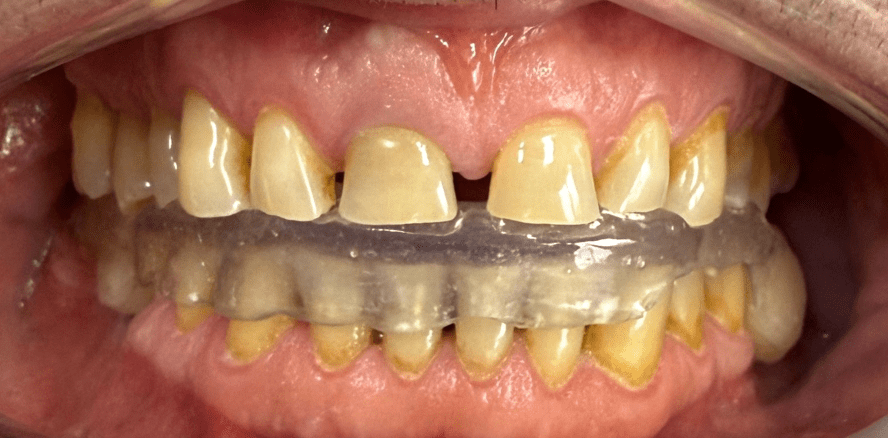

Am folgenden Tag erfolgte eine erneute Konsultation, bei der gemeinsam mit dem Patienten Form und Farbe des Provisoriums evaluiert wurden. Die Zahnfarbe wurde auf VITA A2 angepasst, mit den übrigen Parametern zeigte sich der Patient zufrieden. Diese individuelle Abstimmung garantierte, dass alle relevanten Informationen für die definitive Versorgung vorlagen.Im nächsten Schritt wurden sämtliche digitalen Scans miteinander gematcht (Modellier, Zirkonzahn) und die Modelle via 3D-Druck (Cadspeed) erstellt. Die CAD-Konstruktion der insgesamt 28 Kronen erfolgte mit Prettau 3 Dispersive Multilayer-Zirkon (Zirkonzahn). Für die Frontzähne wurde eine keramische Verblendung (Initial Zr-FS, GC) gewählt, während die Seitenzähne monolithisch mit Prettau 3 Dispersive (Zirkonzahn) gestaltet wurden. Die Bisslage der definitiven Versorgung wurde statisch an die mit der Michigan-Schiene ermittelte Position angepasst. Für die funktionelle Gestaltung der Restauration wurden Gruppenführung und „freedom in centric“ gewählt, um eine physiologische Belastung der Kiefergelenke sicherzustellen.